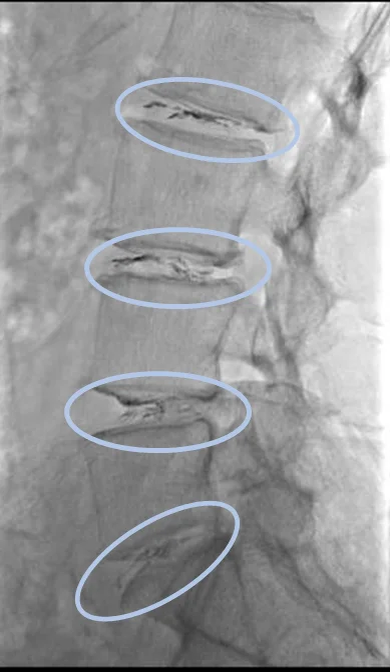

По данным МРТ выявлена дегенерация межпозвоночных дисков L2/L3, L3/L4, L4/L5 и L5/S1, стеноз позвоночного канала на уровне диска L3/L4, вызванный смещением позвонка L3, а также межпозвоночная грыжа диска L3/L4 и левосторонний фораминальный стеноз на уровне диска L4/L5.

Стеноз позвоночного канала и межпозвоночная грыжа диска L3/L4, а также дегенерация диска и фораминальный стеноз L4/L5 являются основной причиной болей.

Проведена селлгель-терапия на дисках L2/L3, L3/L4, L4/L5 и L5/S1.